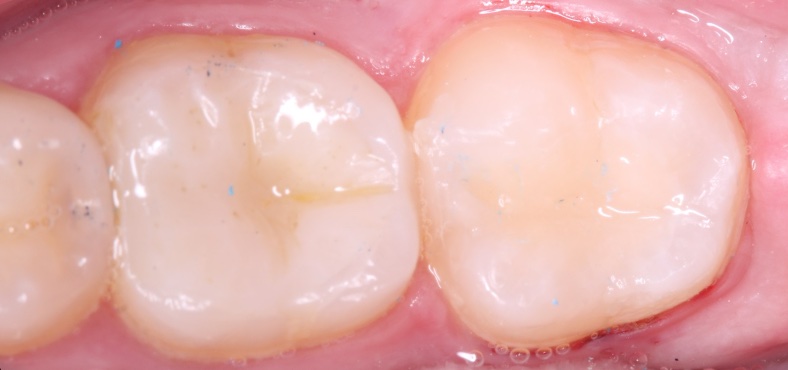

Наши работы